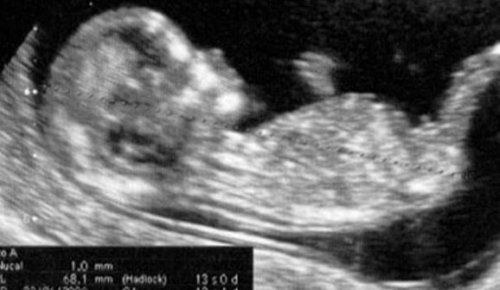

Hamileliğin ilk üç aylık dönemi sonunda yapılan ultrason kontrolü eğer hala yapılmamış ise bu dönemde yapılabilir.

İlk üç aylık dönemin sonunda yapılan ultrason kontrolü hamileliğin başından itibaren annenin deneyimlediği tüm kontrollerin son aşamasıdır.

Bu noktada ilk üç aylık dönemin gelişimi tamamlanmış olur.

Özellikle ilk defa anne olan kişiler için en zor ve stresli dönemin sonlandığını söyleyebiliriz.

Kısa bir süre için de olsa sağlık kontrollerinin sıklığı azalacaktır.

Aylık kontroller fetüsün gelişiminin sağlıklı olup olmadığının gözlemlenmesi ve annenin herhangi bir rahatsızlık yaşamadığından emin olmak adına son derece önemlidirler.